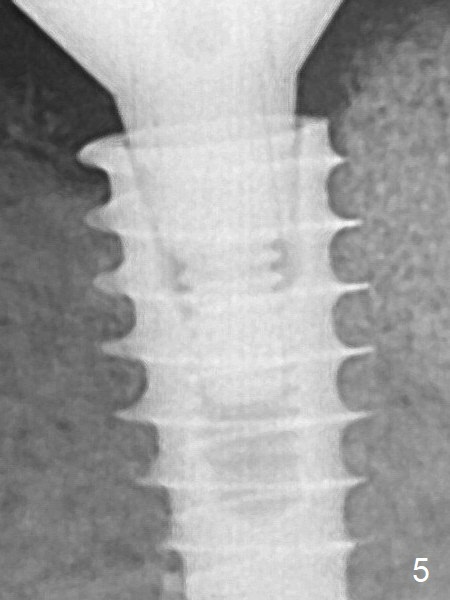

There is no bone loss 1 year 3 months post cementation (Fig.6).